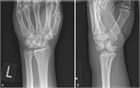

臨床像

舟状骨骨折は14~40歳に好発し,手関節を伸展した状態で手をついて転倒(FOOSH)し,関節可動域(ROM)の減少と手関節(特に橈側の背側)に強い痛みを訴える.身体診察では,変形や斑状出血はみられないが,動作や触診で疼痛を認め,しばしば腫脹もみられる.腫脹は特に解剖学的嗅ぎタバコ入れ(母指を伸展した際に,長母指外転筋と短母指伸筋の腱の間にある,手関節の橈側にみられる窪み.127.1)でみられる.疼痛は軽度のこともあるが,握ったり掴んだりすると悪化する.